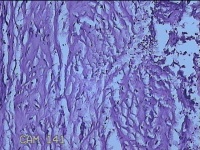

左上后牙根尖肿物

性别

男

年龄

42岁

临床诊断

慢性牙周炎

一般病史

左上后牙残根邀请拔除。

标本名称

大体所见

灰白暗红色肿物1.5x0.8x0.3cm一个,表面光滑,切开肿物呈囊性,囊内有大量脓液,囊壁厚0.2ml,另有牙齿1.5x0.8x0.7cm一颗。